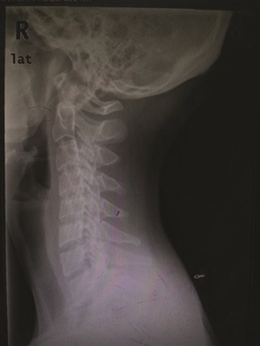

泰勒头颈和身体明显呈一定角度

X光片下已变形的颈椎

非洲原始部落女性,像这样头顶水壶,脖子伸得很直。 上周,第58届格莱美颁奖典礼落幕,美国女歌手泰勒·斯威夫特,这位身高一米八的金发美女一举拿下“年度专辑”等3项大奖。就在前几天,有微信公众号推送一篇文章,指出泰勒有致命缺点——脖子向前伸。 文章说,泰勒的脖子总是往前倾,头颈部和身体呈一定角度。 不过,有研究人员发现,现代人群中,有点脖子向前倾的人还不少。 有研究人类原始姿势的学者Esther Gokhale认为,从远古时期的雕像来看,老底子的人类站立时,脖子都是直的。 Gokhale去了非洲原始部落,观察那里人群的姿态。那里的女性,头顶水壶,脖子伸得很直,全身也是笔直的。她认为,正是因为这些女人颈部姿势正确,才能头顶水壶之类的重物而不会伤到颈椎。 为什么现代人看起来脖子向前倾?Gokhale分析,这与人们久坐不动的时间增加,经常低头看东西有关,“人们缺乏抬头、撑起脖子看远处的活动,所以脖子不自觉地向前伸了。” 这位专家的解释有无道理,我们自己的脖子情况怎么样? 脖子向前伸,是不是一定有颈椎病? 我们在办公室随机做了个小调查,看有多少人的脖子是向前伸的。 25位同事中,基本是三十岁以下的年轻人,昨天下午两点,23位同事坐在电脑前办公。一个个看过来,发现只有三位女同事的脖子没有前伸。 脖子向前伸,是不是一种病? 浙江大学医学院附属第一医院骨科主任林向进主任医师说,脖子向前伸,要分两种情况,一种是生理性的,一种是病理性。 生理性的,人的脖子本来就有韧性,向前向后都可以,经常保持一种姿势,人体习惯了这个体位,脖子就呈向前伸的状态。如果注意一下,人体立即可以恢复正常姿势。 病理性的,就是有颈椎病了,颈椎正常的生理曲度有了改变。正常的颈椎曲度是向前凸的,像一个“(”(见下图),而病理性的曲度变直,甚至反向成为“)”。姿态不太好看,像“乌龟向前伸头”。 “判断颈椎有没有变直或者反弓,不是用肉眼看看就行的,需要拍一张X光片,看清楚每根颈椎和椎间盘的排列。”林向进主任说。

正常的颈椎生理弧线 正常的颈椎有一个凸向前方的生理曲度,生理曲度消失的最初原因是颈部肌肉疲劳,累积到一定程度,颈椎椎间盘病变,椎间盘膨出,压迫神经,就会出现疼痛、胸闷和头晕的颈椎病症状了。 门诊中颈椎病年轻患者增多 他们的脖子也是向前伸 林向进主任医师说,门诊中的颈椎病患者有不少是脖子向前伸的,固定一个姿势,让他们脖子竖起来,都会喊疼。 省中山医院推拿科专门看颈椎病和腰椎病,科室主任吕立江教授说,门诊中超过一半的患者是来看颈椎病的,相对来说,颈椎比腰椎更容易受伤,颈椎附近的肌肉比腰椎要少,更容易受到不良姿势的影响。 本来颈椎病是种“退行性病变”,年纪大了,身体器官用得久老化了,发生了病变。“可现在年轻人得颈椎病的越来越多,主要是他们不注重颈椎健康,保持不良姿势,颈椎提前老化,得了颈椎病。” “最近,有个17岁的学生患者,到我们这里看颈椎,他的样子很特别,头向左前方伸出,好像跳街舞时被定格了。”吕主任说。 寒假就要结束了,他和爸妈约定,最后放松一下:连续三天,他都在夜以继日玩游戏——白天电脑游戏,晚上躲在被窝里玩手机游戏、看视频。前天,骑电动车上同学家玩,被冷风一吹,在一个街口转弯时,脖子被“卡牢”了。 吕主任说,这位学生的颈椎病其实还算轻的。“一直保持一个姿势玩电脑、手机,颈部肌肉劳损了,冷风一吹,肌肉僵硬,这还不是颈椎的问题。如果一直按现在的频率折腾颈椎,颈椎间盘突出等严重的颈椎病,迟早会找上门。” 林主任看门诊有这个感觉,“年轻的颈椎病患者越来越多,他们大多也是喜欢玩电脑、手机。” 浙江大学医学院附属第二医院骨科陈其昕教授说,门诊中经常有会计、文案、IT行业的患者,颈椎病算是他们的职业病。“现在智能手机越来越普及,又有一些新工种加入,比如手机App开发师、手机游戏开发师、微信编辑等。” 颈椎病患者中,手机族比电脑族的病情更有特点,“看手机,头低得更厉害,还合并腱鞘炎;电脑族则比手机族多了腰痛,颈椎不好,腰椎也不好。” 颈椎变形 能恢复到正常生理曲度吗? 陈其昕教授说,颈椎生理曲度,医学上把通过X光片上颈椎向前的弧形凸起称为“颈椎生理曲度”。颈椎生理曲度的存在,能增加颈椎的弹性,减轻和缓冲重力的震荡,防止对脊髓和大脑的损伤。由于长期坐姿、睡姿不良和椎间盘髓核脱水退变,颈椎的前凸逐渐消失,甚至变直或呈反张弯曲,即向后凸,这是颈椎病通过X光片诊断的重要依据之一。 “早期的颈椎弧度变直,仅仅是一个颈椎肌肉疲劳的信号,如果不当回事,颈椎仍旧超负荷工作,积累到一定程度,就会发生颈椎病。” 如果患者出现心慌、胸闷、头晕等交感神经症状,症状越来越顽固,这时颈椎弧度改变就不是单纯的肌肉疲劳信号,而是神经交感型颈椎病的表现;如果颈椎弧度变直并有肢体麻木、胳膊疼痛、走路踩棉花感等脊髓压迫的表现,应该到医院做个颈椎核磁共振检查,是否合并有脊髓型或神经根性颈椎病的可能。 “大家照镜子、拍X光片,发现颈椎生理曲度改变,不要惊慌,不要以为脖子变直了就一定是颈椎病,如果是早期的肌肉疲劳,稍微改变一下坐姿习惯,颈椎的生理弧度会慢慢恢复正常,不会恶化成颈椎病。”陈教授说。 怎么保护颈椎? 试试专家的“仙鹤点水”操 远离颈椎病,应注意两点:一是改变不良姿势,二是,坚持多活动。 怎么活动?大家熟悉的“米字操”,在专家看来,要因人而异。“有些椎间盘型的颈椎病患者,不能做旋转型的运动,不能动得太快,否则,做了反而会加重病情。”林向进主任说。 省中山医院的吕立江教授有套颈椎保健操,几个动作,锻炼颈椎。吕教授经常在门诊里教患者做,大家反响不错。